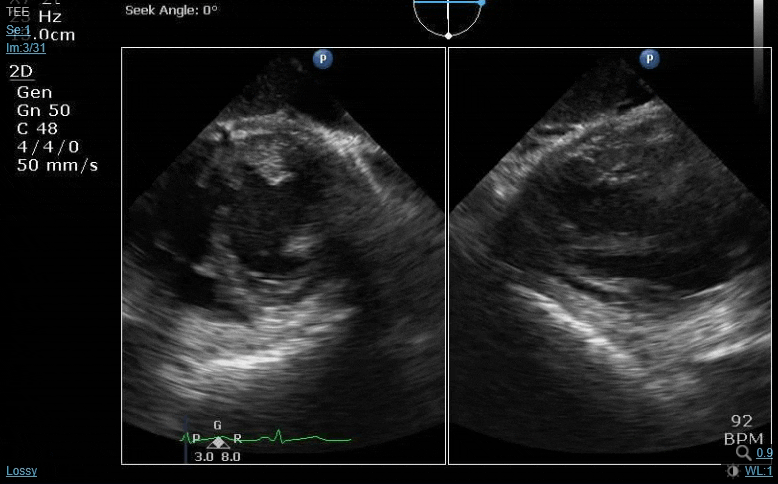

77 y/o male scheduled for a TAVR.

The following images are acquired after induction.

Thoughts?

The spectral Doppler trace tells an interesting story- looks like there are 2 separate obstructions to aortic outflow. The valve itself does look calcified and fairly immobile, so the AS may be real. Second (later peaking) obstruction looks like it might be a subaortic membrane? The color Doppler pattern is textbook for SAM, but the muscular IVS doesn’t look that thick and we don’t see any leaflet SAM in any of the 2D shots you posted.

In terms of what to do next, that’s a challenging question. I don’t think I’d advise proceeding with the TAVR until the anatomy is further delineated. I know it’s not the correct modality for this, but curious what the TAVR CT scan looked like?

Looks like subaortic membrane + probably AS. I think the discussion above was exactly what needs to happen. That is, consult CT surgery, wake up the patient and talk about surgical intervention.

1) There is a really significant PISA on the LV side of the mitral. In addition, CFD shows at least moderate MR. Possibly rheumatic appearing? Wonder what the gradient was across the MV. Need more images

2) Significant RA compression. Don't really know what to make of it in this setting

3) There are definitely two obstructions, one in the LVOT (? Subaortic membrane) and another across the AV. This is shown with both the CFD and CWD. However, it doesn't have the general appearance of a subaortic membrane. Looks more filamentous and mobile. Possible Emboli risk?

Classic SAM appearing CFD.

At least moderate to severe MR

Severe AS.

Septal hypertrophy.

I can see where some would think that there is redundant anterior mitral valve leaflet but on close inspection this looks and smells like a sub aortic membrane. This suspicion is validated by the 2 peaks on CWD and a peak gradient of 200 mmHg def. puts SAM into the picture.

So… TAVR and sub aortic membrane plus SAM is a def. no IMO for TAVR. Morbidity related to landing a Sapien 3 is def. increased.

We woke this patient up and brought him to the OR:

Septal myectomy

Root enlargement

Resection of sub aortic membrane

23mm Edwards Magna

Post bypass echo:

Mean gradient 6 mmHg

Mild residual SAM with no significant LVOT obstruction. Peak gradient 12 mmHg.

Mild to Moderate MR

Below you can see the sub aortic membrane we resected.